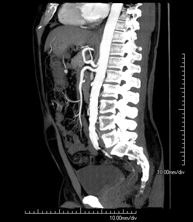

Prova diagnòstica no invasiva que consisteix en l'estudi de l'artèria aorta abdominal a través de l'obtenció d'imatges d'alta definició anatòmica mitjançant l'ús d'un equip de TC (Tomografia Computeritzada) i de contrast iodat. La qualitat de les imatges permet realitzar reconstruccions en 2D i 3D gràcies a estacions de treball especialitzades en l'estudi arterial. Està indicat en aquells pacients amb malaltia vascular (arteriosclerosi), en aneurismes d'aorta, en pacients amb dolor abdominal de possible origen vascular, en estudis prequirúrgics de lesions adjacents a l'aorta abdominal com a "mapa" vascular. La informació obtinguda de manera no invasiva és indispensable per als pacients que requereixen tractament percutani o quirúrgic. En aquells pacients que només requereixen seguiment de les lesions vasculars, aquesta tècnica és la tècnica no invasiva d'elecció juntament amb l'angio-RM. - Angio-TC Artèries renals

Prova diagnòstica no invasiva que consisteix en l'estudi de les artèries renals a través de l'obtenció d'imatges d'alta definició anatòmica mitjançant l'ús d'un equip de TC (Tomografia Computeritzada) i de contrast iodat. La qualitat de les imatges permet realitzar reconstruccions en 2D i 3D gràcies a estacions de treball especialitzades en l'estudi arterial. Està indicat en aquells pacients amb malaltia vascular (arteriosclerosi), en aneurismes d'aorta, en pacients amb dolor abdominal de possible origen vascular, en estudis prequirúrgics de lesions adjacents a l'aorta abdominal com a "mapa" vascular. La informació obtinguda de manera no invasiva és indispensable per als pacients que requereixen tractament percutani o quirúrgic. En aquells pacients que només requereixen seguiment de les lesions vasculars, aquesta tècnica és la tècnica no invasiva d'elecció juntament amb l'angio-RM. - Angio-TC Aorto-ilíac

Prova diagnòstica no invasiva que consisteix en l'estudi de les artèries ilíaques i l'aorta abdominal a través de l'obtenció d'imatges d'alta definició anatòmica mitjançant l'ús d'un equip de TC (Tomografia Computeritzada) i de contrast iodat. La qualitat de les imatges permet realitzar reconstruccions en 2D i 3D gràcies a estacions de treball especialitzades en l'estudi arterial. Aquesta prova està especialment indicada com estudi prequirúrgic (mapa vascular) abans d'intervencions percutànies o quirúrgiques d'aorta abdominal, com l'estudi complementari en pacients amb isquèmia de membres inferiors, etc. - Colonoscòpia virtual

A non-invasive diagnostic test that involves studying the abdominal aorta by obtaining high-definition anatomical images using CT (computed tomography) equipment and iodinated contrast. With the aid of workstations specialised for arterial studies, the image quality supports 2D and 3D reconstructions. It is indicated in patients with vascular disease (atherosclerosis), aortic aneurysms, abdominal pain of possible vascular origin, pre-surgical studies of lesions adjacent to the abdominal aorta as a vascular ‘map’, etc. Information obtained non-invasively is indispensable for patients requiring percutaneous or surgical processing. In patients who only require tracking of vascular lesions, this technique is the non-invasive technique of choice, together with MRI angiography.